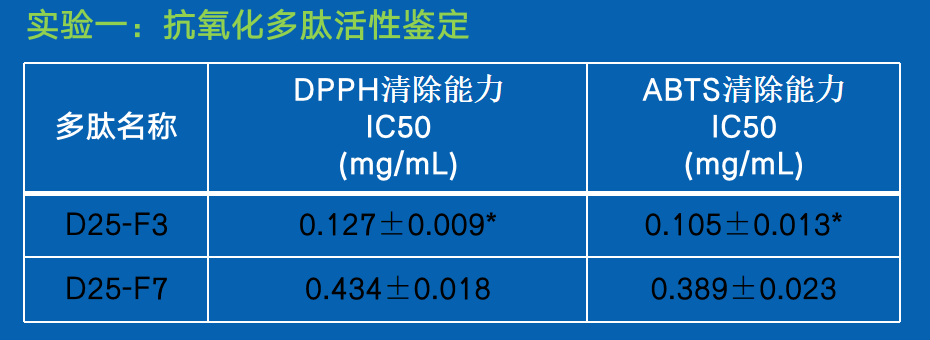

实验一:抗氧化多肽活性鉴定

结论:

SEQ ID NO:1的多肽D25-F3具有更强的抗氧化特性,与SEQ ID NO:2多肽 D25-F7相比针对DPPH清除能力以及ABTS的清除能力均显著提高(P<0.01)。